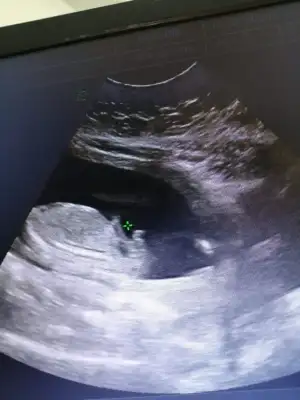

Merhaba kızlar bende temmuz annesi olacağım nasip olursa şuan 17+2 haftalik gebeyim ve tüp bebekle gebe kaldim. Doktorum bana 12. Haftada erkeğe benziyor dedi dün kontrolde ters duruyor çok zor görmek ama kız bu bebek dedi. Bende ikilem yaşamaktansa dün özel bir muayenehanesi olan bir doktor var yüksek kalite ultrason cihazlarla bakıyor ve ayrıntılı bakıyor bebeğin damarlarına kadar görüyor ona gittik. Ama cinsiyetle ilgili hicbirsey sormadık o herseyine baktıktan sonra biliyorsunuzdur heralde bebeğiniz erkek dedi ben tekrar şok dedim kız bebek dediler bize dedim doktor güldü hayır kesin erkek dedi ve testislerini ve pipisini gösterdi. Şimdi ben tekrar gittiğimde farklı birsey söylenecek diye stres içindeyim bebeğime bir zibin almak istedim onu bile alamadım dün. Cinsiyetin fotosunda ekliyorum kızlar çok zormuş bu durum

erkek e benziyor gerçi ben pek anlamam ama ayrıntılı da bakmışlar sonuçta bence çok yanılmaz olmaz bu saatten sonra:)